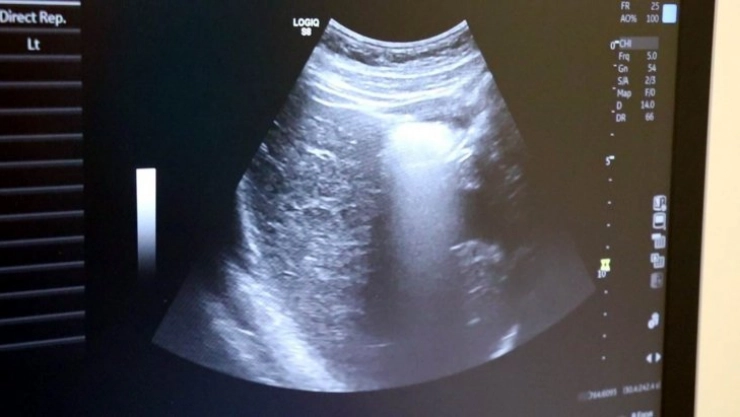

Ayrıntılı ve 4 boyutlu ultrason ile bebeklerin doğmadan önceki sağlık durumlarının belirlenebileceğine değinen Uzm. Dr. İlker Eroğlu, “Ultrason; yüksek frekanslı ses dalgalarının bilgisayar işlemcisinde işlenip, kablo arayıcılığıyla monitöre aktarılmasıdır. Son yıllarda gebelikte ayrıntılı ultrason gerekliliği giderek artmaktadır. Yaklaşık 50 yıl önce ultrason yaygın değilken doğumlarda bebek nasıl doğacak, sağlıklı mı sağlıksız mı doğacak ya da cinsiyet bile bilinemiyordu. 4 boyutlu ultrasonda ya da ayrıntılı ultrasondan sonra bebeğin sakatlıkları doğumdan önce anlaşılıp, tedavisi mümkün olanlar da doğumdan önce tedavi edilebilir oldu. Böylelikle bebeklerin daha sağlıklı olarak dünyaya gelmesi sağlanmış oldu. O nedenle ayrıntılı ultrason gereklidir” dedi.

Renkli ultrasonlarda bebeklerin anne karnındayken sakatlığı olup olmadığının belirlendiğini ifade eden İlker Eroğlu, “4 boyutlu ultrason halk arasında ‘renkli ultrason’ diye bilinir. Anneler bu ultrasonda bebeğin görüntüsünü anladığı için onu daha çok sever. Hekimler genelde ultrasona siyah-beyaz bakar. 4 boyutlu ultrason iç organlar hakkında detaylı bilgi vermez. Biz detaylı ultrasonda (2. düzey ultrason) bebeğin iç organlarına yönelik incelemeyi siyah beyaz olarak yaparız. O nedenle bizim için siyah-beyaz ve 2 boyutlu olarak yapılan inceleme daha önemlidir. 4 boyutlu ultrasonda da faydalandığımız yerler vardır. 4 boyutlu ultrasonda örneğin; bebeğin kolu-bacağı yoksa, dudak yarığı varsa, gösterebiliriz. Çeşitli anatomik deformasyonları da anneye gösterebiliriz. Hala dünyada ayrıntılı ultrason 2 boyutlu ve siyah-beyaz olarak yapılır” diye konuştu.